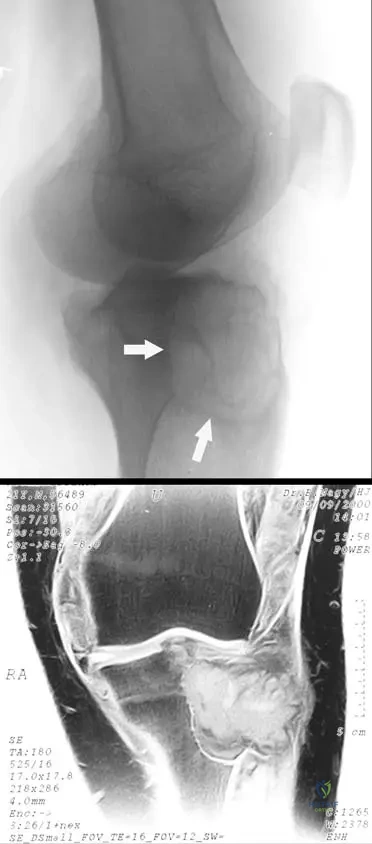

A 38-year-old male presents with chronic left knee pain and swelling. Initial radiographs are obtained.

View Answer & Explanation

Correct Answer: B

Rationale: In the early stages of PVNS, radiographs often show periarticular lucencies and considerable effusions (soft tissue swelling). The clinical photograph (Fig. 10.5) shows visible swelling of the knee. Main Distractor: A) Extensive subchondral bone cysts and joint space narrowing. While these can occur in long-standing PVNS due to destructive changes and secondary degeneration, periarticular lucencies and soft tissue swelling are more characteristic early findings.

Question 11

A 42-year-old female presents with long-standing, progressive left knee pain and swelling. She has a history of recurrent effusions. A lateral radiograph of her knee is shown.

Correct Answer: C

Rationale: The provided text states that "At long duration, the destructive proliferation of synovial-like tissue can affect the adjacent bone," leading to erosive changes as seen in Fig. 10.6a. Main Distractor: B) Secondary osteoarthritis due to cartilage loss. While secondary degenerative changes may be present, the primary cause of the extensive erosive changes in PVNS is the direct destructive proliferation of the synovial tissue into the bone, not solely cartilage loss.